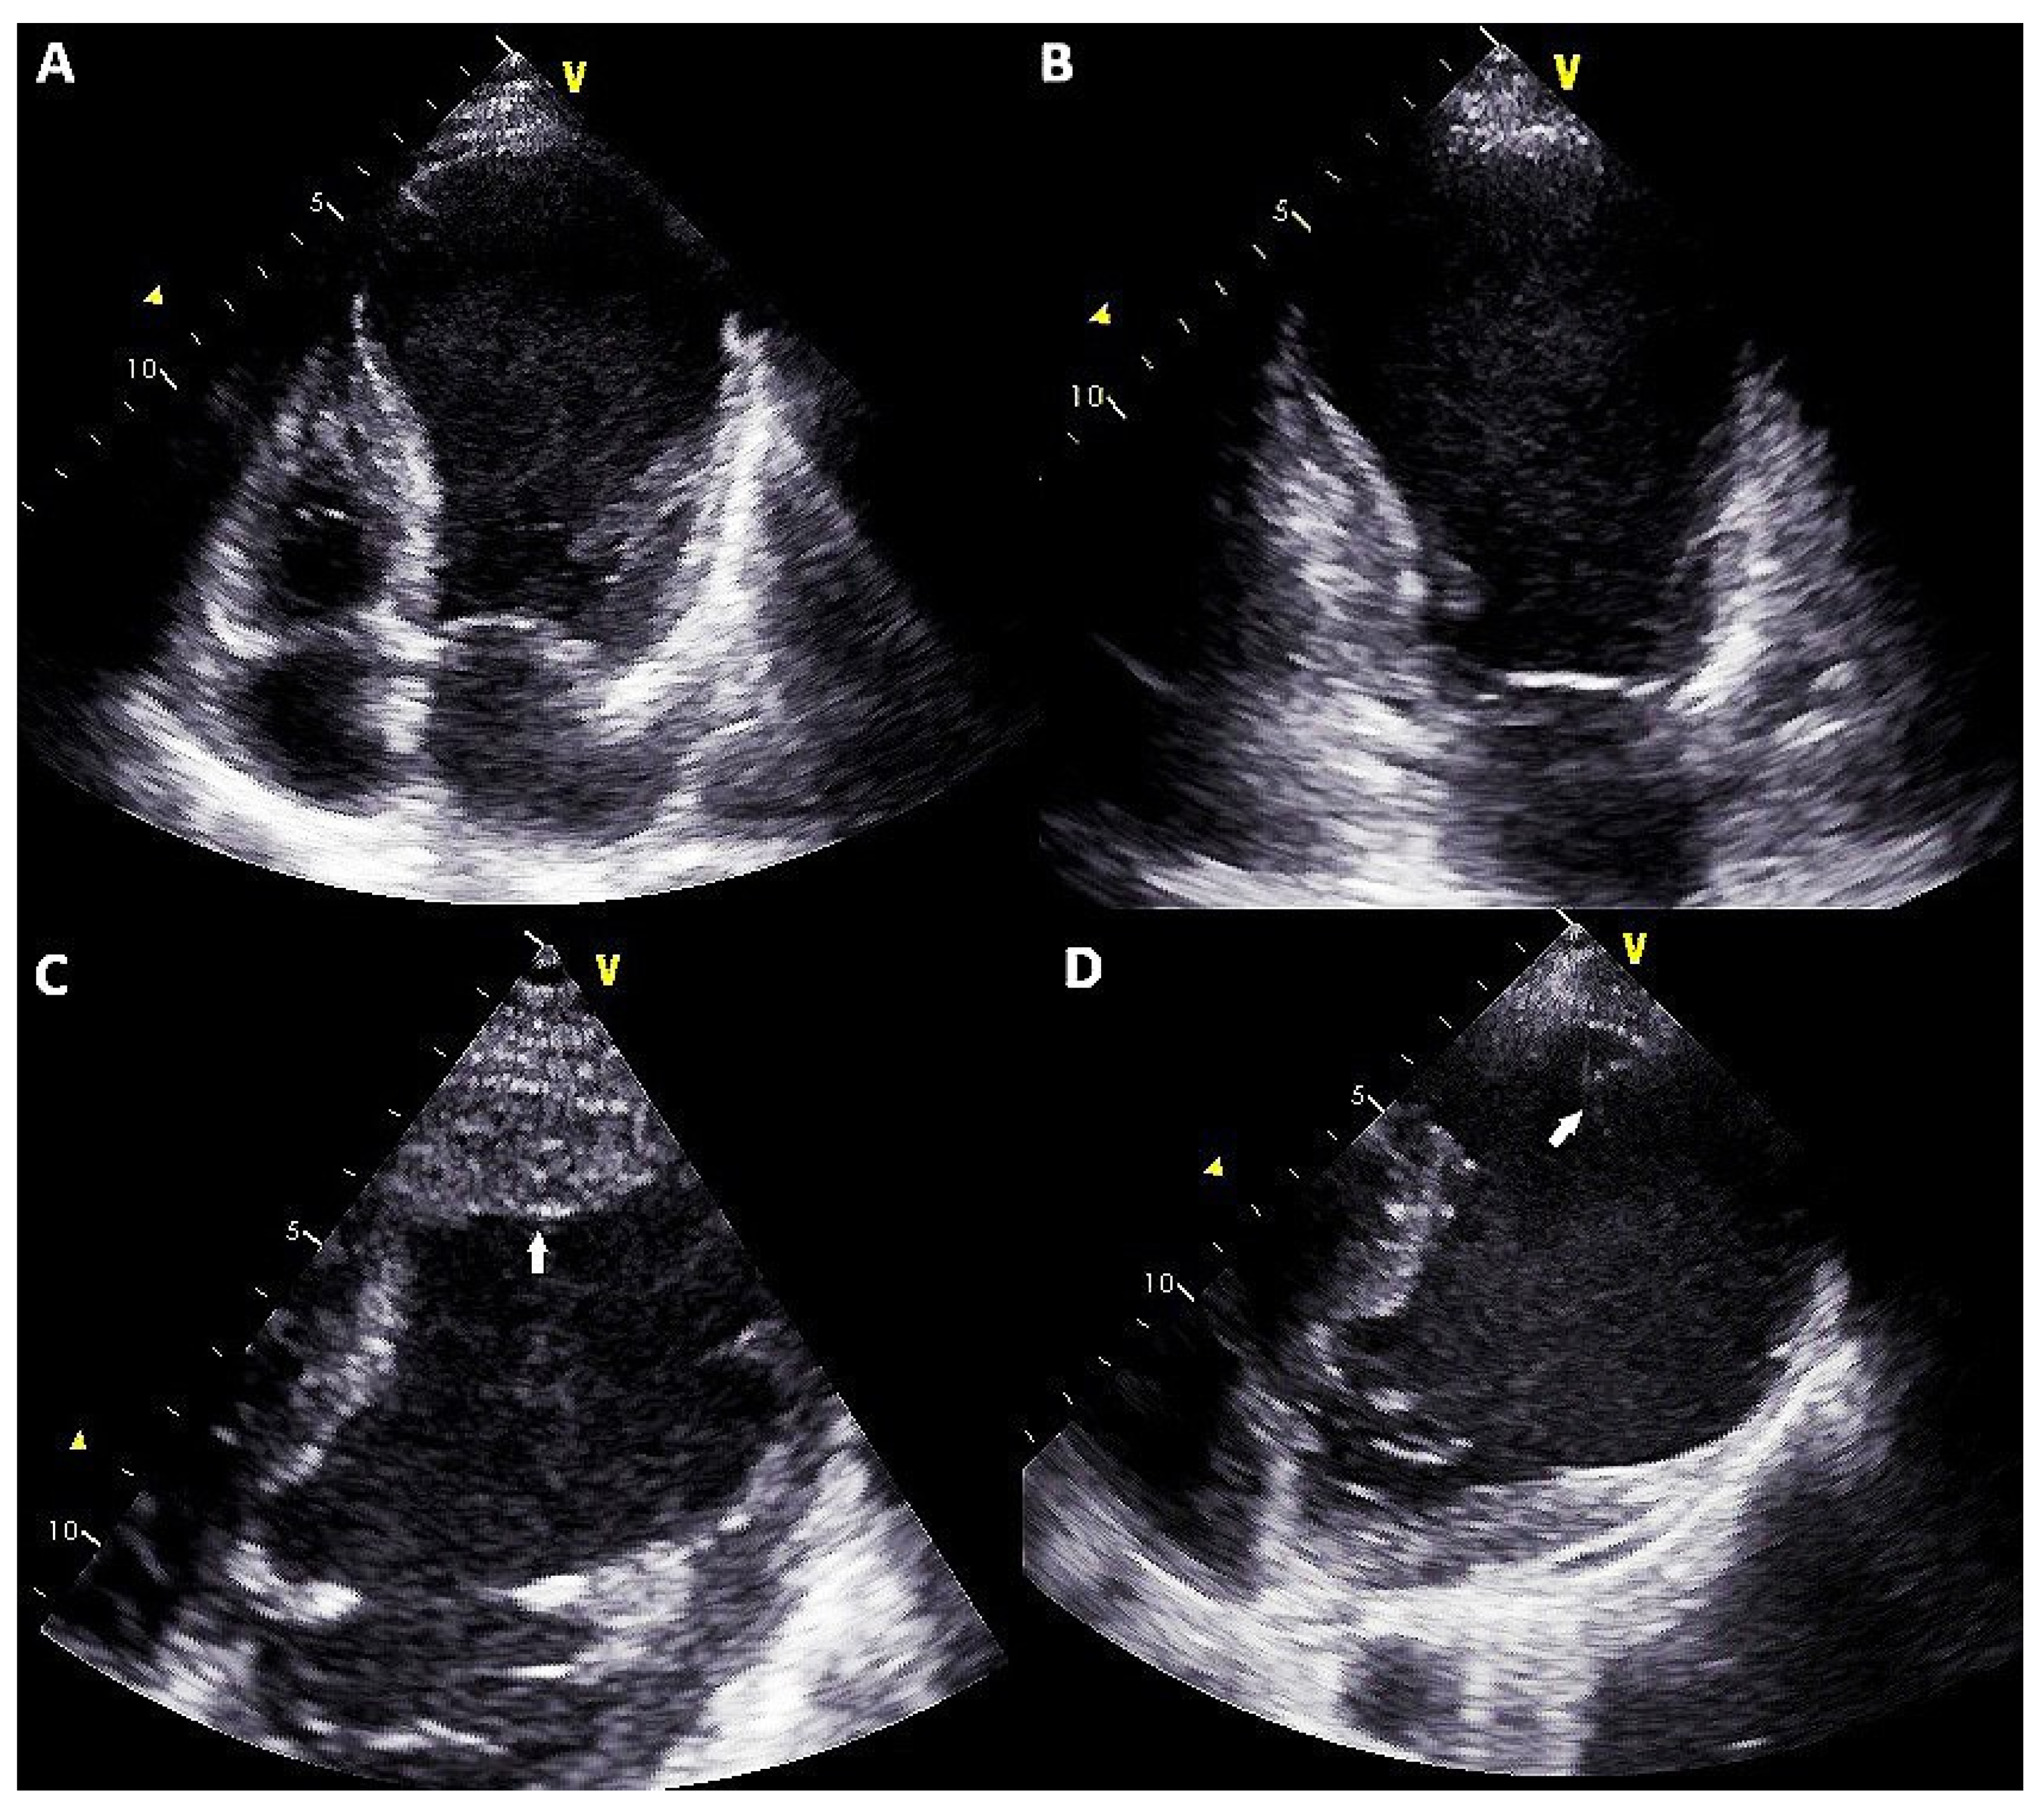

| 12 May 2020 | Hospitalization for acute heart failure with diagnosis of ischemic dilated cardiomyopathy with severe reduction of ejection fraction and thrombosed apical aneurysm Clinical presentation was complicated by acute kidney injury (eGFR at admission 38 mL/min/m2 vs. 57 mL/min/m2 of March 2020) and acute liver injury (biluribin 3.5 mg/dL, AST 560 UI/L, ALT 654 UI/L) High dose diuretics therapy (furosemide 250 mg bid plus spironolactone 200 mg/die) and levosimendan infusion was started (0.1 mcg/kg/min) |

| 18 May 2020 | Heartmate III implantation with and concomitant surgical plication of the anterolateral wall pseudoaneurysm |